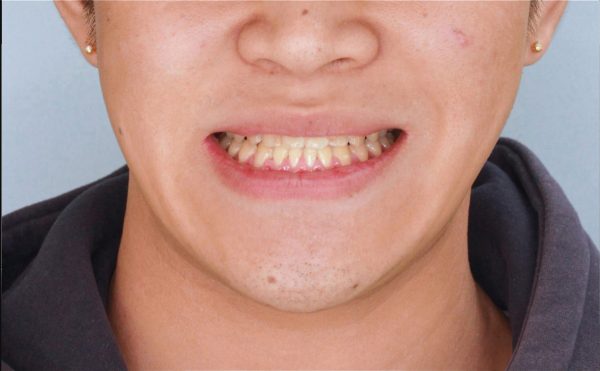

噛めない!「 手術しないで治してほしい 」18歳 男性 骨格性開咬

18歳の 男性です

「 噛めないので、治してほしい 」との事で来院されました。

正面から見たところです。 こう見えても噛んでいる状態です。

奥歯は接触していますし、口を開けている訳ではありません。

とにかく 噛めないとの頃、この状態では全く噛めないです

開咬(かいこう)という状態ですね

正面からです。口が大きく開いていて、閉じられません

しっかりと噛み合わせてもらっている状態です